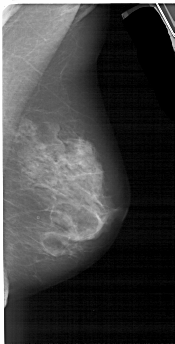

A_1553_1.RIGHT_MLO

RIGHT_CC LINES 4936 PIXELS_PER_LINE 2476 BITS_PER_PIXEL 12 RESOLUTION 43.5 NON_OVERLAY

RIGHT_MLO LINES 5146 PIXELS_PER_LINE 2611 BITS_PER_PIXEL 12 RESOLUTION 43.5 NON_OVERLAY